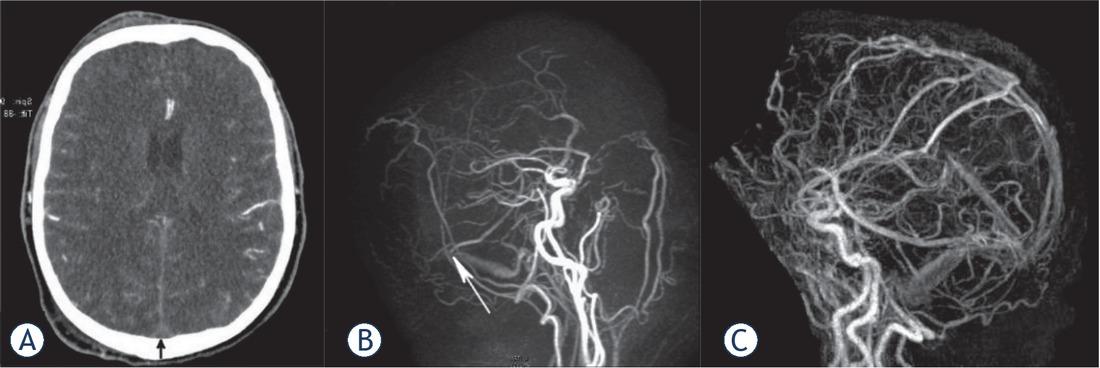

A 59-year old man was examined after 5 days of headaches and a seizure. CT revealed bilateral cortical subarachnoid hemorrhage (SAH) and moderate diffuse brain edema, but no hemorrhagic infarction was formed (A). An extensive thrombosis of cerebral sinuses/veins including the superior sagittal sinus, transversal sinuses, left sigmoid sinus and jugular bulb was observed. The right transversal sinus was occluded to the point of Labbe vein inflow (B), arrow showing confluence of vein to sinus). Fractured heparin and later warfarin were introduced; the patient scored 0 according modified Rankin Score (mRs) at control examination. Complete recanalization of the occluded sinuses occurred (C).